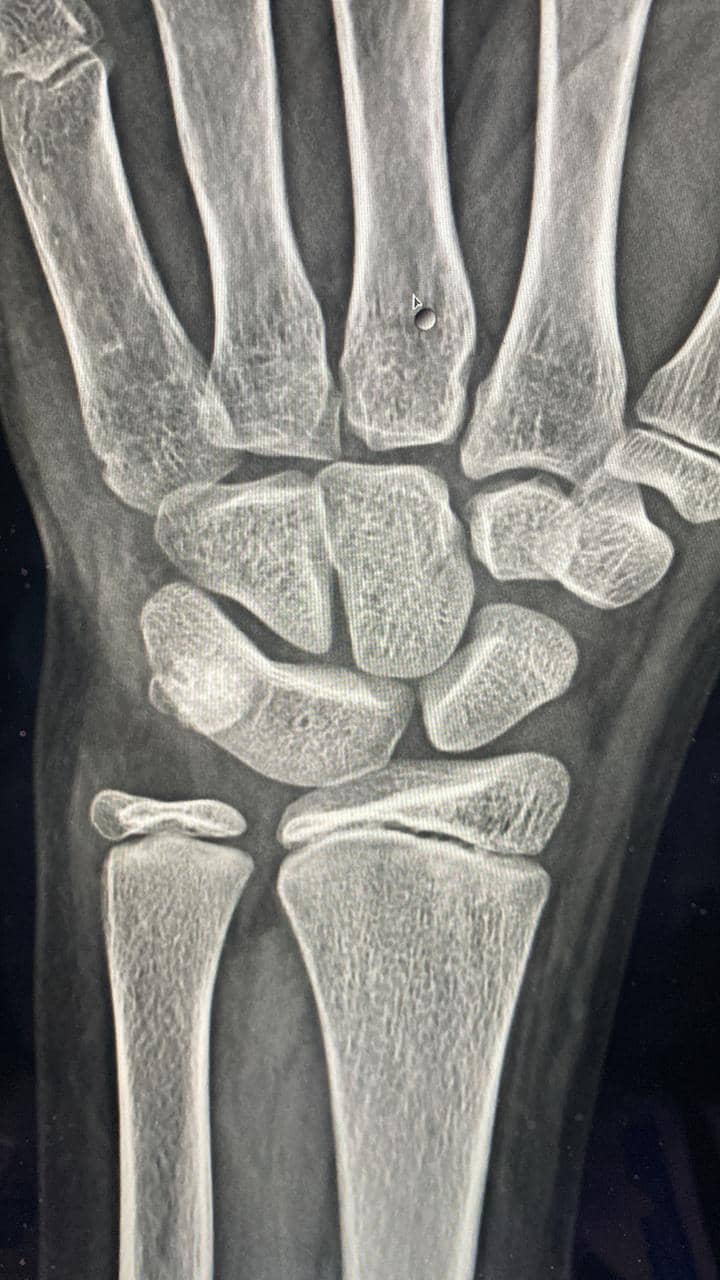

Lunotriquetral coalition

• Congenital fusion of the lunate and triquetral bone.

• Like all coalitions it can be osseous, fibrous or cartilaginous. The latter two would be difficult to pick up on radiographs.

• Asymptomatic in most cases requiring no further management.